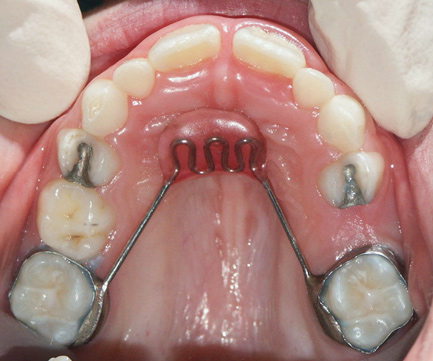

Tongue and thumb pressures also contribute to a high-vaulted palate, which can lead to mouth breathing (Figure 11).31 Additional risks exist for infection and callus development on the thumb. Ideally, the child should quit this habit by age 4, before permanent occlusal changes develop.32 Quitting can be achieved through positive reinforcement and by offering the child comfort during thumb-sucking triggers. The use of bitterants (eg, Mavala Stop, Thum, Control-It!), which are painted on or rubbed into the thumb, is another option.33 A habit breaker appliance may also be utilized if these techniques are unsuccessful. Devices such as a palatal crib, rake, or bluegrass appliance interfere with the thumb and tongue habits and allow the bite to passively close.34 The author recommends utilizing a habit breaker appliance for 6 to 9 months and maintaining reinforcement for a few months once the habit is eliminated (Figure 12 through Figure 14).

Fig 12. Palatal crib used to passively close bite and break thumb-sucking habit, at delivery (Fig 12), 6 weeks (Fig 13), and 12 weeks (Fig 14).

Figure 12

Fig 13. Palatal crib used to passively close bite and break thumb-sucking habit, at delivery (Fig 12), 6 weeks (Fig 13), and 12 weeks (Fig 14).

Figure 13

Fig 14. Palatal crib used to passively close bite and break thumb-sucking habit, at delivery (Fig 12), 6 weeks (Fig 13), and 12 weeks (Fig 14).

Figure 14